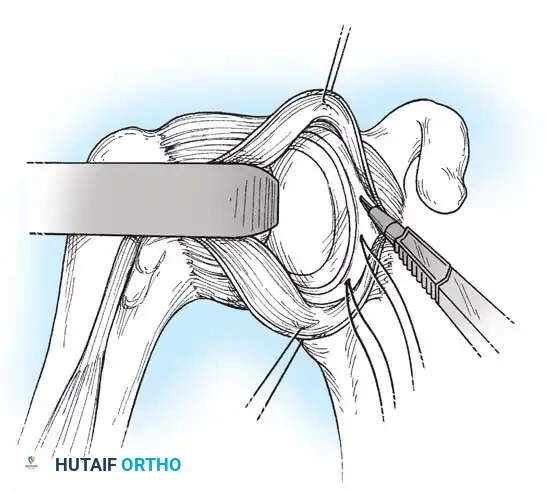

- A Fukuda retractor is placed within the joint to retract the humeral head laterally and posteriorly, exposing the anterior glenoid rim and labrum.

Glenoid Preparation and Labral Repair

The essential step in restoring stability is the anatomical reduction of the capsulolabral complex to a bleeding bone bed on the anterior glenoid rim.

- Debridement: The anterior glenoid neck is decorticated using a motorized burr, rasp, or osteotome to create a bleeding cancellous bed. This promotes robust biological healing of the repaired labrum.

- Mobilization: The scarred, medially displaced labrum (ALPSA lesion) must be fully mobilized using a periosteal elevator until the subscapularis muscle belly is visible anteriorly. The tissue must float freely to be shifted superiorly and laterally.

- Anchor Placement: Suture anchors (typically 3 to 4) are placed along the articular margin of the anteroinferior glenoid (from the 5:30 to 3:00 positions for a right shoulder). Anchors must be inserted at a 45-degree angle to the articular surface to maximize pullout strength and avoid joint penetration.

Capsular Shift and Closure

To address capsular redundancy, an inferior capsular shift is performed.

- The arm is positioned in 30 to 45 degrees of abduction and 20 degrees of external rotation.

- The inferior capsular flap is advanced superiorly and laterally, tensioning the IGHL complex. The sutures from the anchors are passed through the shifted capsule and tied.

- The superior flap is then brought down over the inferior flap in a "pants-over-vest" fashion to reinforce the anterior wall and close the rotator interval.